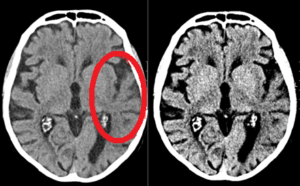

Acute infarct on plain CT head